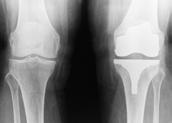

Predstavniki iz gospodarstva in javnega sektorja so na dogodku predstavili dobre prakse in izkušnje pri uvajanju rešitev za brezpa pirno poslovanje. Raul Rodman je predstavil, kako so v Poslov nem sistemu Mercator z elektronskim upravljanjem in hrambo dokumentov zmanjšali obseg papirja in dosegli ključne prednosti, kot so nadzor nad procesi, večja varnost in dostopnost dokumen tov ter večje zadovoljstvo uporabnikov. Peter Sušnik, vodja službe za upravljanje z dokumentarnim gradivom v UKC Ljubljana, pa je prikazal, kako so v tej osrednji zdravstveni ustanovi s pomočjo rešitev za brezpapirno poslovanje vzpostavili nadzor nad obvlado vanjem dokumentov sistema vodenja ISO.